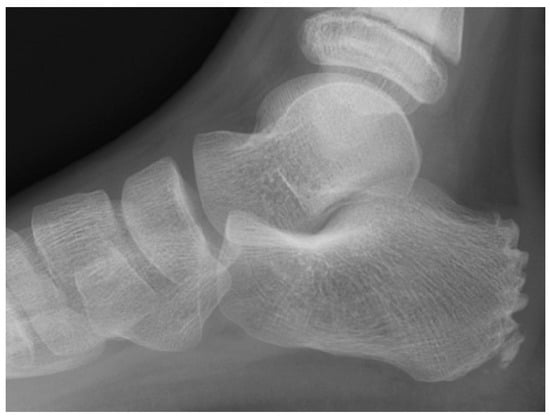

Figure 3.

Eleven-year-old male patient. Radiograph (left) demonstrating typical fragmentation and bipartite appearance of the calcaneal apophysis. MRI (right) showing detailed fragmentation with associated bone marrow edema.

Figure 4.

Ten-year-old male patient. Radiograph (left) revealing marked fragmentation, thinning, and bipartition of the calcaneal apophysis. MRI (right) demonstrating extensive associated bone marrow edema.